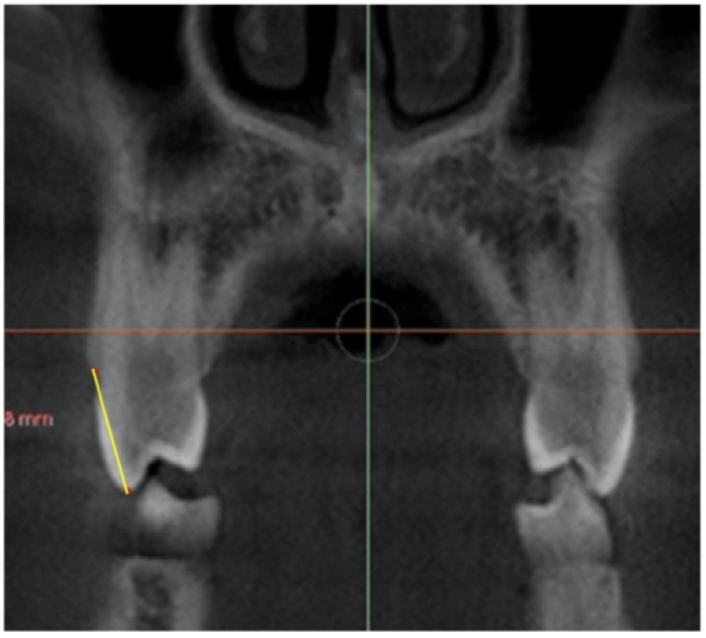

| Buccal alveolar bone crest level (BACL) | Distance from the tip of buccal cusp to the buccal bone crest of first and second premolar, and from the mesiobuccal cusp of first molar crown, to the buccal bone crest in the first anterior coronal cut describe for each tooth, on the right (R) and left (L) side. | ![]() |